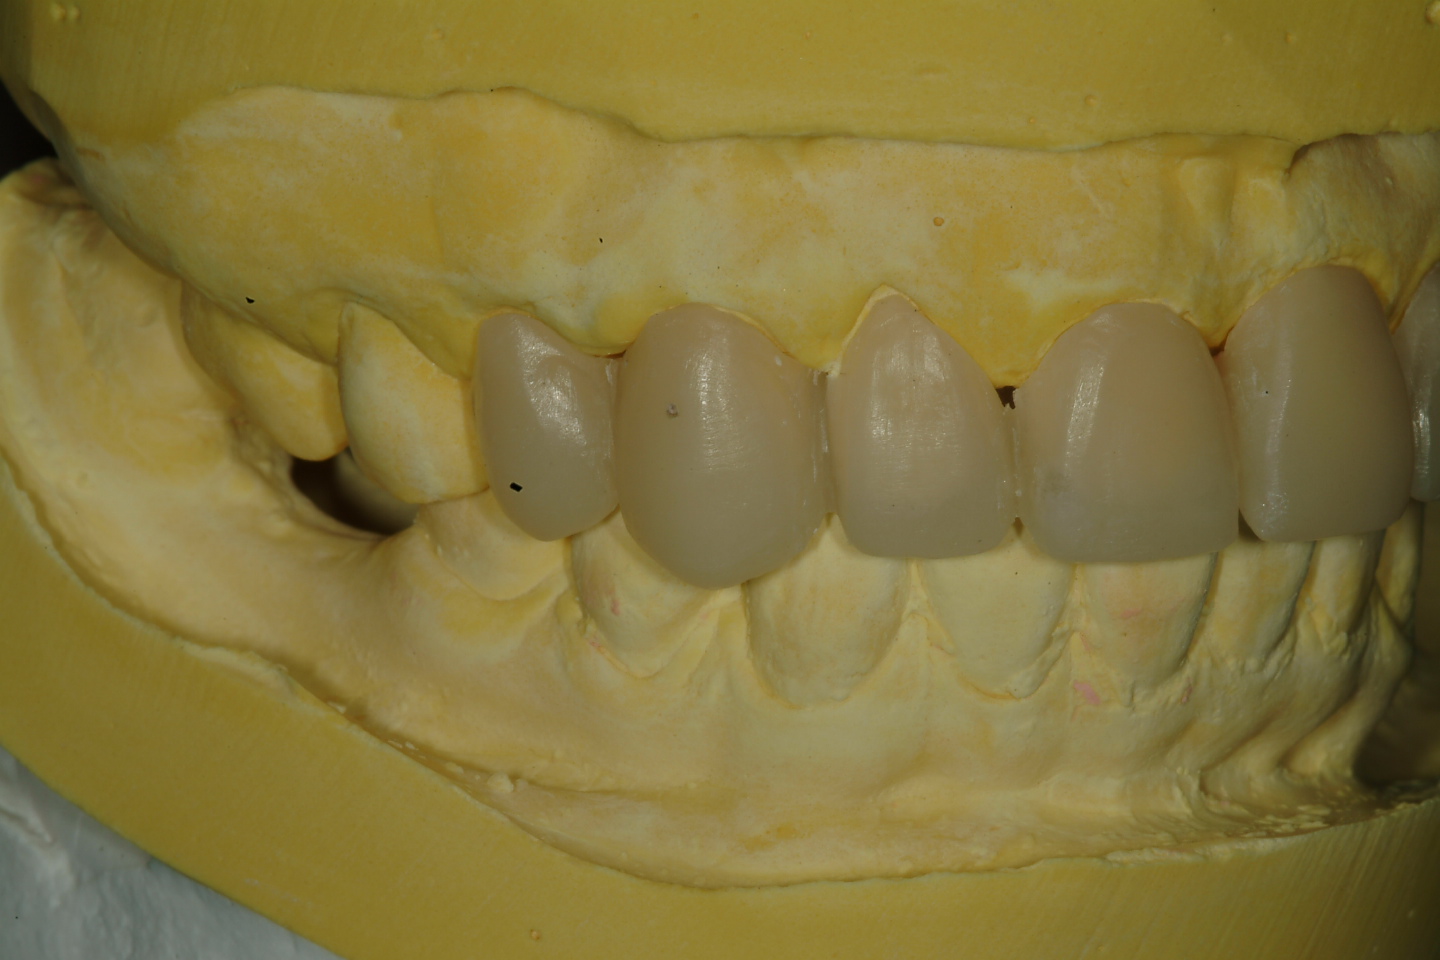

三、上咬合器後 , 與病患討論未來假牙外型(圖三)

圖三 |